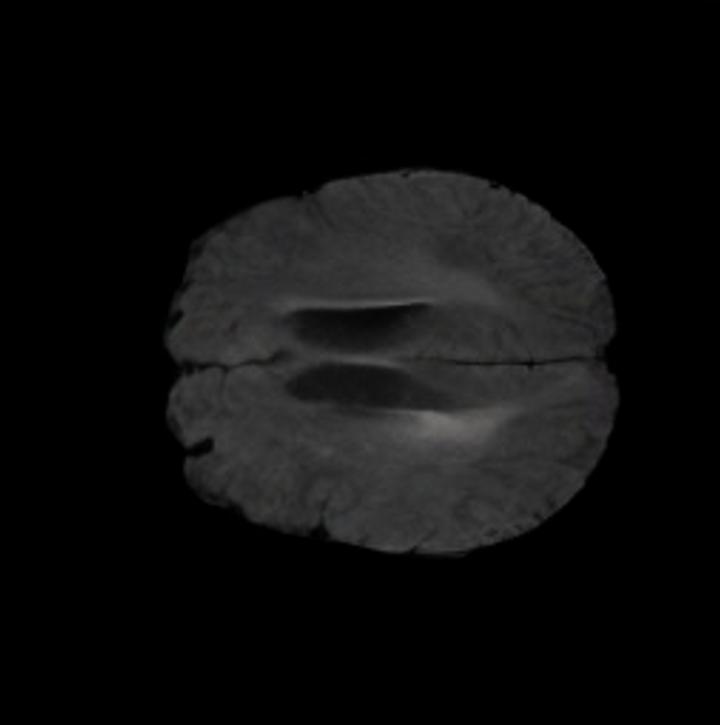

Notably, X-Diffusion achieves sota dB for a few input slices while baselines require more than 60 input slices to achieve similar performance (Figure 7). The margin is more than 12 dB PSNR for the 1-slice input in both the BRATS and the UK Biobank benchmarks (see Table 1 and Figure 6). For reference, two randomly sampled MRIs from the UK Biobank would have a PSNR of 15.95 dB 0.36 (on 4800 randomly sampled examples). The slices from 3D reconstructed volumes at varying depths and axis of rotation visually match the ground truths (see Figures 5 and Figure 4). We also plot the error map (Figure 4) of such X-Diffusion generations to highlight the differences with the ground truth MRIs.

Brain Volumes Preservation. The generated MRIs by our X-Diffusion retain almost the exact same average brain volume vs of the real MRIs.

Tumour Information Preservation. For the brain tumor segmentation, we use a Swin UNETR model[27, 70], trained with random rotation, and intensity as data augmentation. In Figure 5, we highlight the tumor profiles of the generated MRIs compared to the ground truth tumour profile. In the test set with human ground-truth annotations (), the real MRI Dice score is 85.15 while the generated MRIs from a single slice have a dice score of 83.09. This shows how the generated MRIs indeed preserve the tumor information and can act as an affordable and informative pseudo-MRI, before conducting an actual costly MRI examination in hospitals.